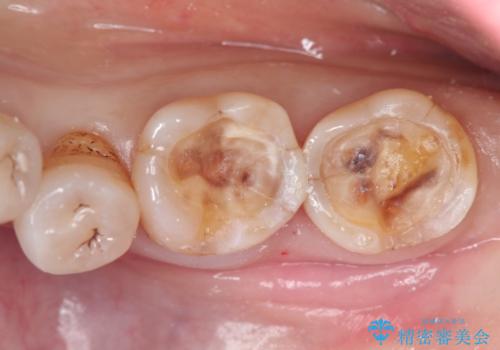

- 以前治療したところがしみて、アイスが食べられないから被せものの治療をしてほしいと来院された患者様です。

咬合が強く、歯牙にマイクロクラックが入っている状態でした。歯髄は保存可能と診断され、フルジルコニアクラウンによる治療を行いました。

咬合面に広範囲の修復物がある状態で中心に強い力が加わると歯牙は外方性の歪みが生じ、マイクロクラックができます。これを防ぐには、咬頭被覆するアンレー、もしくはクラウンによる治療が必要です。